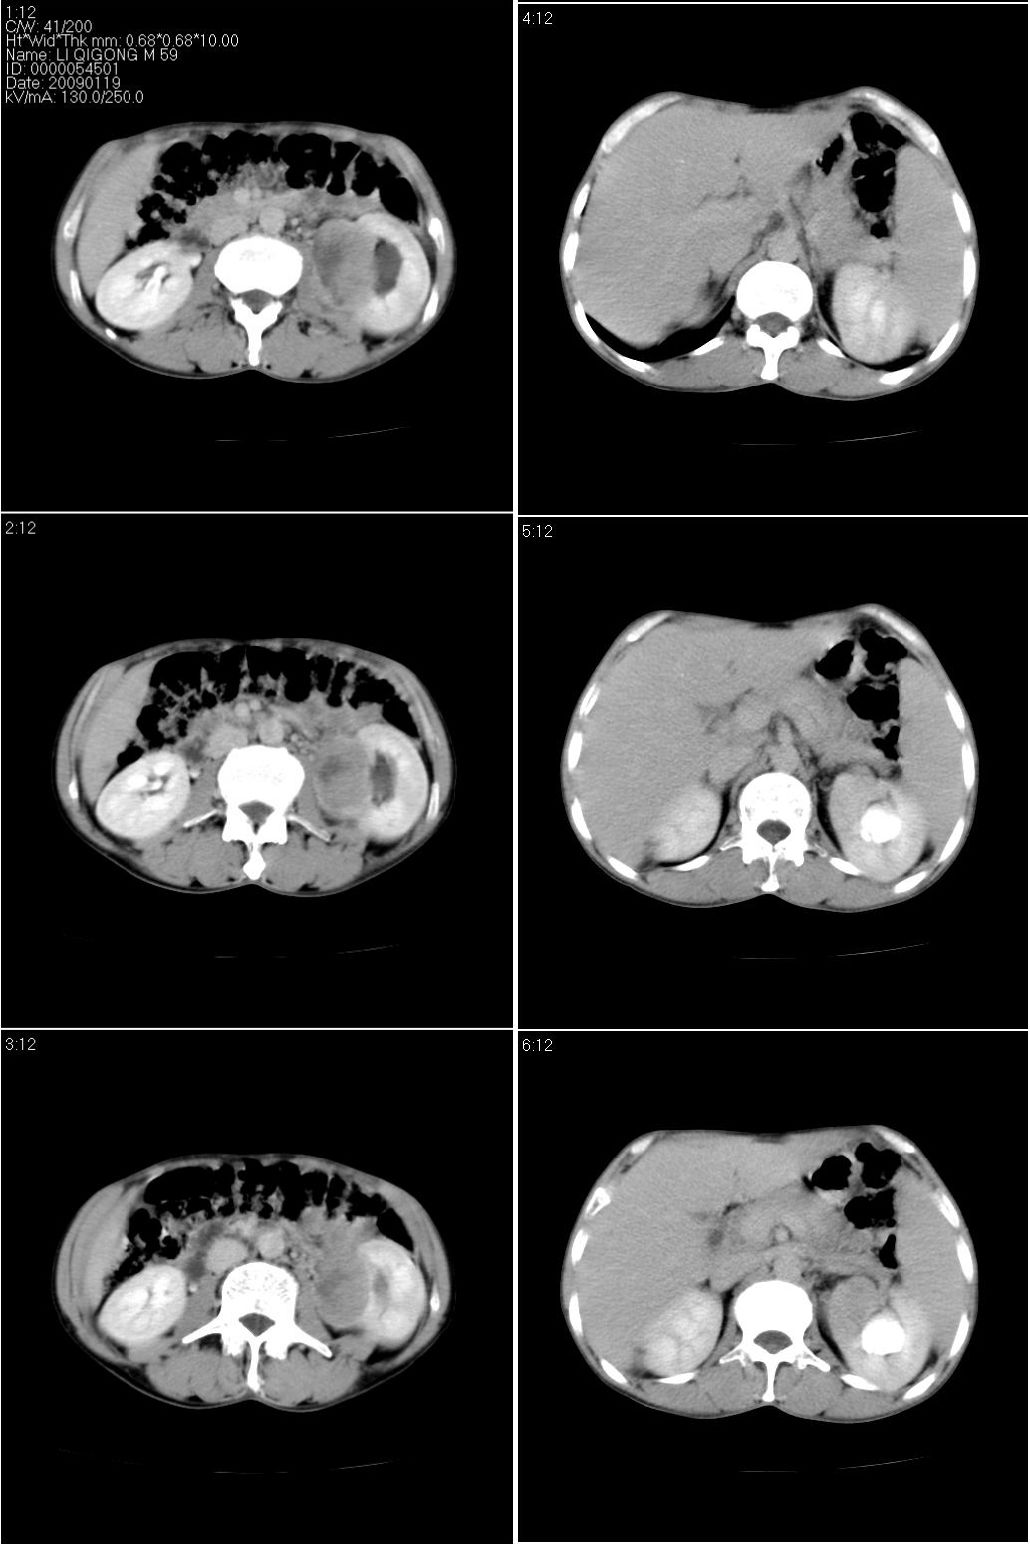

标题: CT17771:男性,59岁。体检发现左肾占位。

男性,59岁。体检发现左肾占位。自诉无尿血、尿痛。

无痛无血尿,左肾实质占位,有明显强化,中心坏死不规则,应该肾癌无疑。

应该考虑左肾癌并肾盂积水

2、左肾占位,呈不均匀性强化,中央有无强化的坏死区。

3、左肾门旁有侧枝开放,提示左肾静脉癌栓形成可能。

4、患者自诉无血尿,但不一定镜下无血尿。

支持 考虑左肾癌并肾积水。

考虑左肾癌并肾盂积水。

考虑左肾癌并肾积水。